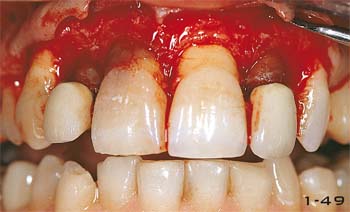

Abb. 1-49 Chirurgische Kronenverlängerung an den oberen Frontzähnen.

Abb. 1-50 Die neue Position der Gingiva und des Knochenkammes unmittelbar nach der Knochenresektion.